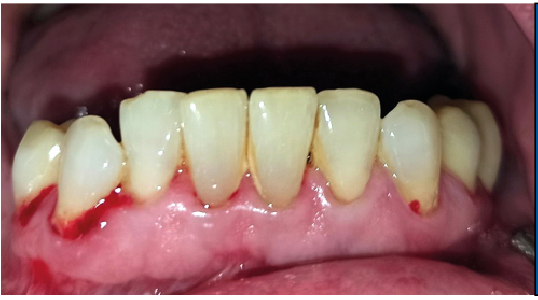

Deutlich mehir Sulkusblutung nach Sondierung auf der paretischen

Seite (4. Quadrant) als auf der nicht peretischen Seite (3. Quadrant)

Die Plaque-Kontamination war in Bezug auf den API auf der paretischen Seite um 10,9 % (p = 0,004) höher als auf der nicht paretischen Seite. Ebenso wiesen die vestibulären Zahnoberflächen der paretischen Seite mehr Biofilm auf als die der nicht paretischen Seite (p = 0,002; s. Tab. 3, Abb. 2a und b). Dabei war der Unterschied bei den männlichen Patienten (0,8 vs. 0,5; p = 0,001) größer als bei den weiblichen Patienten (0,6 vs. 0,4; p = 0,002). Außerdem wurde bei Patienten mit rechtsseitiger Fazialisparese ein größerer Seitenunterschied (0,7 vs. 0,5; p < 0,001) dokumentiert als bei Patienten mit linksseitiger Fazialisparese (0,5 vs. 0,4; p = 0,043). Ursächlich erschien die Händigkeit der Patienten. Während bei Patienten mit linksseitiger Fazialisparese die Erkrankung auf der für Rechtshänder besser zu reinigenden Mundhälfte vorlag, waren rechtshändige Patienten mit rechtsseitiger Fazialisparese einer doppelten Belastung ausgesetzt (18). Die Gingivablutung nach Sondierung war auf der paretischen Seite ebenfalls signifikant höher als auf der nicht paretischen Seite (s. Tab. 3). Das spiegelte sich sowohl bei den Werten des SBI (s. Tab. 3, Abb. 3) als auch bei den Werten des PBI (s. Tab. 3, Abb. 4a und b) wider. Die Sondierungstiefen waren auf der paretischen Seite im Vergleich zur nicht paretischen Seite tiefer und der Attachmentverlust war höher. Dabei konnte jedoch kein signifikanter Unterschied nachgewiesen werden. Der mittlere PSI erreichte auf der paretischen Seite signifikant höhere Werte als auf der nicht paretischen Seite